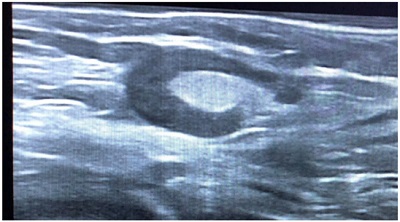

Niño de 7 años que tras vacunación de SARS-CoV-2 presenta bultoma axilar derecho generando asimetría a nivel pectoral. Asintomático. En la exploración física: adenopatía de consistencia elástica, móvil y dolorosa a la palpación. Se realiza ecografía objetivando una adenopatía hipoecoica, ovalada de 15 mm de diámetro anteroposterior, bordes hiperecogénicos bien delimitados e hilio llamativamente grande (Fig. 1) con vascularización central (Fig. 2). Diagnóstico de adenopatía reactiva, con seguimiento ecográfico al mes (Fig. 3) y disminución del tamaño.

Figura 1. Adenopatía hipoecoica con hilio grande

Figura 1. Adenopatía hipoecoica.